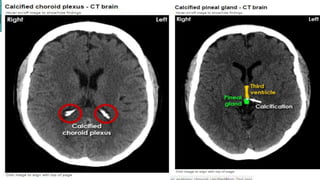

Normal calcification

The pineal gland

PINEAL GLAND